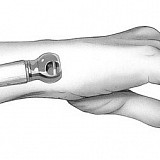

Minimally invasive surgery is a surgery aimed to minimize the area of interference in the body and the degree of tissue trauma. The main techniques using for minimally invasive intervention are laparoscopic (endoscopic) surgery and endoscopy.

Special medical equipment is used, such as fiber optic cables, miniature video cameras and special surgical instruments, which are manipulated through small holes. Images of internal organs are transferred to an external video monitor, and the surgeon can diagnose on the basis of the image and perform the necessary operation.